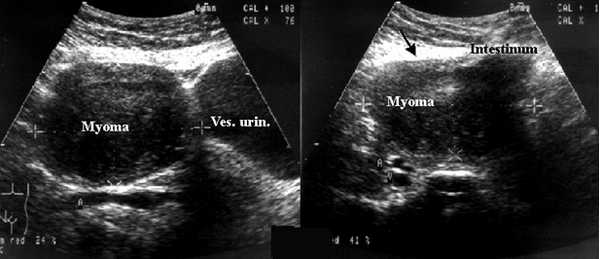

По данным ультразвукового исследования (УЗИ) органов малого таза матка anteversio, -flexio, с четкими, ровными контурами, размерами 52,2 × 45 × 57,4 мм. Стенки не утолщены, структура миометрия однородная. Полость матки не деформирована. М-эхо - 14,5 мм, соответствует 2-й фазе менструального цикла. В проекции левых придатков определяется округлое гипоэхогенное образование размерами 52 × 50 × 50 мм с четкими контурами, с кровотоком по периферии и в центральных зонах, индекс резистентности IR = 0,58, максимальная скорость кровотока (Vmax) - 10 см/с. К образованию прилежит овоидное образование 21 × 15 × 17 мм, объем - V = 2,85 мл. Правый яичник визуализируется, размерами 34 × 29,5 × 31 мм, V = 16 мл, определяются единичные фолликулы до 5 мм. Свободной жидкости в малом тазу до 30-50 мл (рис. 1).

С целью исключения ЗНО яичника пациентке выполнено дообследование с применением УЗИ с внутривенным конт-растным усилением (КУУЗИ). После пункции кубитальной вены введен катетер, через который вводился контрастный препарат Соновью, разведенный в 10 мл физиологического раствора натрия хлорида (0,9%). В течение 102 секунд после внутривенного болюсного введения контрастного препарата в дозе 2,0 мл (в артериальную фазу) определяется стойкое контрастное усиление новообразования. Определен тип васкуляризации - существенная смешанная периферическая и центральная васкуляризация. По отношению к окружающим тканям вымывание замедленно до 2,5 минут (150 сек). Также при введении контрастного препарата отмечается контрастирование «ножки» образования, позволяющее предположить, что оно связано с маткой и является субсерозным миоматозным узлом на тонком основании (рис. 2).

Учитывая отсутствие убедительных клинико-инструментальных данных за злокачественную природу новообразования, преимущественно основываясь на данных КУУЗИ, было принято решение о выполнении лапароскопии в условиях гинекологического отделения. Лапароскопию выполняли по традиционной методике. При ревизии органов брюшной полости и малого таза обнаружили, что печень, сальник, видимые петли кишечника без видимой патологии. Спаечного процесса нет. В латеральных карманах - без видимой патологии. Матка в размерах не увеличена, серозная оболочка бледно-розового цвета, гладкая, блестящая. В позадиматочном пространстве - серозный выпот до 50 мл. Маточные трубы - без видимой патологии. Правый яичник подпаян к заднему листу широкой связки, после мобилизации в размерах несколько увеличен, содержит желтое тело диаметром 20 мм. Образование, определяющееся в области левых придатков, представляет собой миоматозный узел с субсерозным ростом, диаметром до 6 см, на тонком основании, расположенный в области левой собственной связки яичника (рис. 3). Питающая ножка и сам узел содержат сосуды диаметром до 0,5 см. Это объясняет выраженный кровоток в образовании по данным УЗИ с внутривенным контрастированием. При осмотре левого яичника - уменьшен в размерах до 1,5 см (последствие ранее перенесенной операции), фолликулярный аппарат выражен слабо. Ножка основания миоматозного узла скоагулирована биполярным электородом, узел отсечен, отправлен на гистологическое исследование (рис. 4).